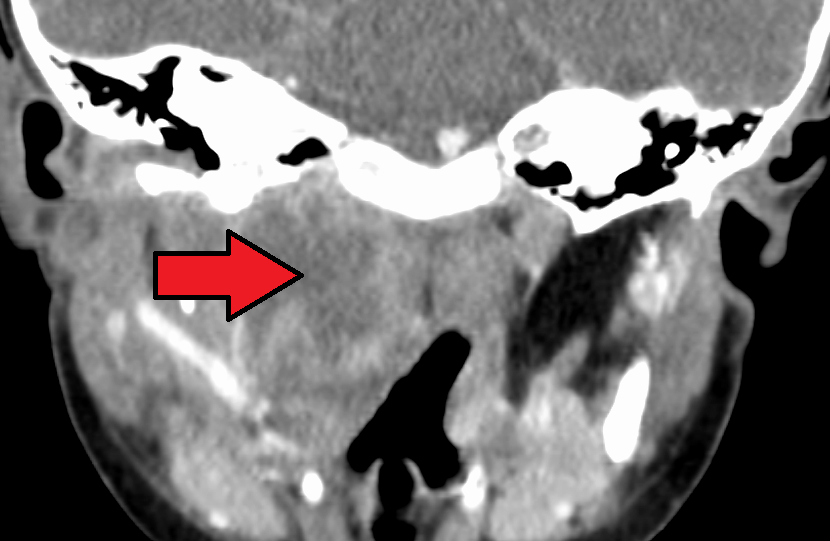

CT에서 보이는 큰 인두후농양

CT 스캔은 확실한 진단 영상 검사이다.[4]

목의 X-레이는 종종(80%의 경우) 영향을 받은 사람의 인두후 공간의 부기를 보여준다. 인두후 공간이 C2 척추의 크기의 절반보다 크면 인두후농양을 나타낼 수 있다.[5] 혈액 검사에서 백혈구 수 증가, CRP 수치 상승을 보이는 경우가 많다. 경부 측면 X선 사진(경부 신전위, 흡기 시 촬영)에서 인두후벽-경추 전면 간 거리는 C2-3 레벨에서 소아, 성인 모두 7mm 이내, C6 레벨에서 소아 14mm 이내, 성인 22mm 이내가 정상이다. 이를 초과하는 경우 인두후벽의 종창이 시사된다. 인두후농양과 급성 후두개염은 증상만으로는 감별이 어려울 수 있으므로 적극적으로 경부 조영 CT를 시행하여 진단을 내린다.